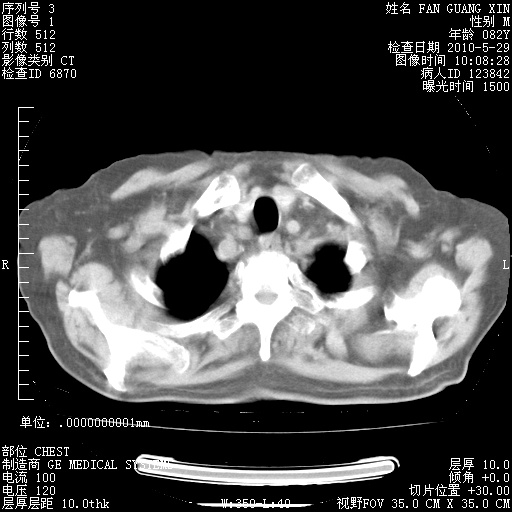

治疗3周后的肺部CT纵隔窗

再治疗10天后的肺部CT 纵膈窗

阅读此次胸部CT,肺间质渗出性改变较入院时有吸收。目前从体温、白细胞、中性分叶明显增高,肯定存在细菌感染(发生医院感染哦,若无消化道及泌尿系统等感染的依据,肺部感染可能大)。若你院头孢哌酮舒巴坦钠耐药率较高,同意你的方案,若48小时体温仍高,可考虑使用碳青霉稀类抗菌药物,同时可予超声雾化、注意滴数时加大液体量。白蛋白33.30g/L较低哦,需加强营养等支持治疗。